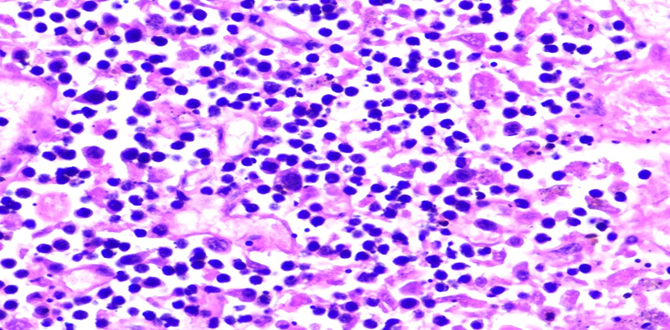

Figure 5B: Photomicrographs showing hemophagocytosis by macrophages in bone marrow (H&E, 40X magnification).

Bone Marrow: Hypercellular marrow (70% cellularity) with trilineage hematopoiesis. Many hemophagocytic cells are identified. Trabecular bone is unremarkable. CD68 and CD163 highlights hemophagocytic activity. CD61 highlights megakaryocytes. Iron: minimal iron storage; could be suboptimal due to decalcification of bone.

Respiratory System: Sections of the right and left lungs show variable areas of vascular congestion, emphysematous changes, intraalveolar edema, and interstitial stromal acute and chronic and inflammation with focal interstitial fibrosis. Pleural fibrin adhesion and subpleural acute and chronic inflammation are identified. Clusters of intravascular histotypes identified, highlighted with CD68 and CD163. Granulomas, fungal forms, viral cytopathic effects, dysplasia, and malignancy are not seen. Special stains of GMS, GRAM, PAS and Iron support the findings. (Figures 4, 5A-C, 6A-D, 7A-C).